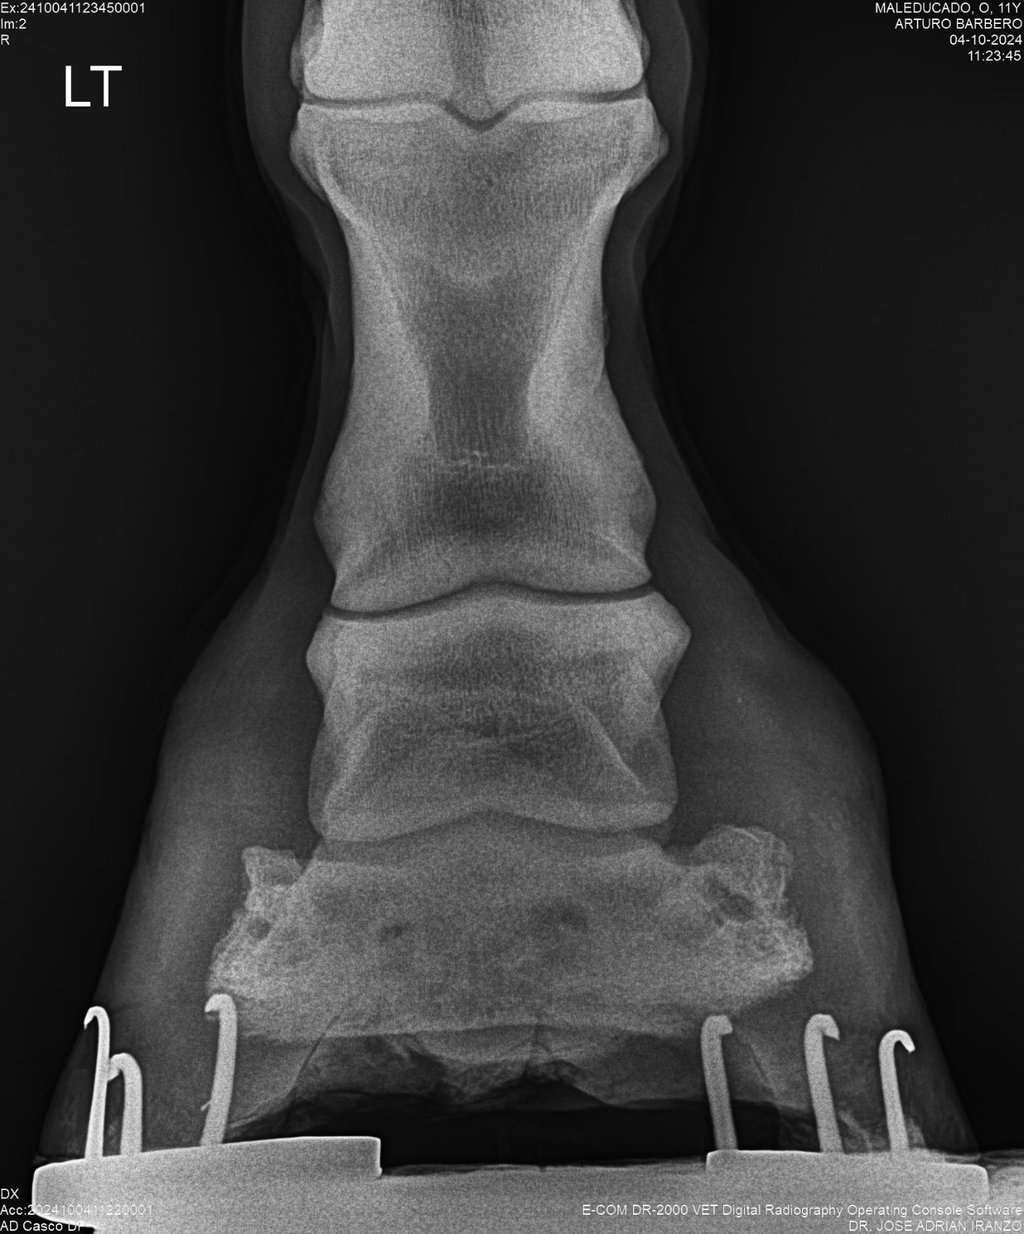

Te guiare paso a paso para desarrollarte en la clinica equina y en el diagnostico de patologias osteoarticulares, tendinosas y ligamentosas del aparato locomotor equino

DIAGNOSTICO POR IMAGENES: ECOGRAFIA Y RADIOGRAFIA